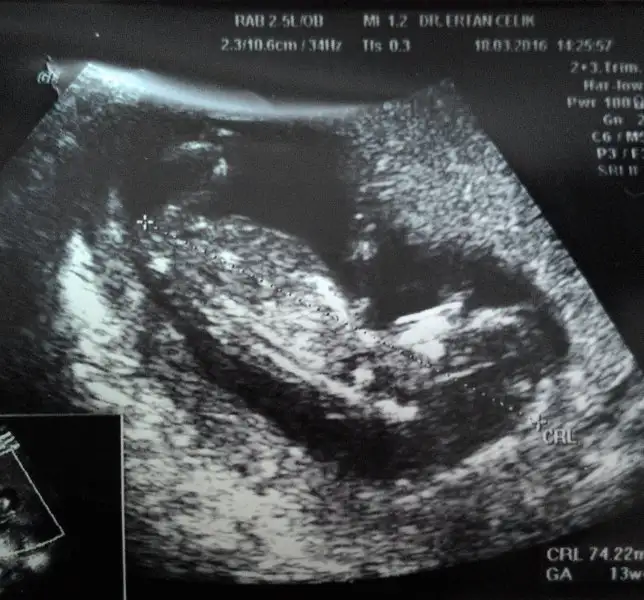

İlk bebişin mi canım. Ben doktoruma direkt sordum. karından ultrasonda plasentasi solda görünüyorsa gerçekte sagda imiş. Usg vajinal ise plasenta diyelim ki solda görünüyor gerçekte de solda imiş. Bende bu teori tutmadı canım. Ama tutan çok fazla hamile var. Benim iki oglumunda plasentasi soldaydı. Plasentanın gerçekte solda olması kız bebek demek.bhchrk cnm sende istersen koy goruntuyu bakalim sana ne dicekler :) bana kiz dedi pikolata78 bi heyecan kapladi icimi hayirlisi tabi herseyin bizimkisi sadece merak :)

Ilk benek olcak hayirlisiyla cnm :) bu plesenta dedigin benim gonderdigim resimde alt tarafta parlak olan sey mi oluoİlk bebişin mi canım. Ben doktoruma direkt sordum. karından ultrasonda plasentasi solda görünüyorsa gerçekte sagda imiş. Usg vajinal ise plasenta diyelim ki solda görünüyor gerçekte de solda imiş. Bende bu teori tutmadı canım. Ama tutan çok fazla hamile var. Benim iki oglumunda plasentasi soldaydı. Plasentanın gerçekte solda olması kız bebek demek.

Burda sırtını dönmüş canım nub gözükmüyor. Allah gönlüne göre verir inşallah canimvalla bi doktor baya kıza benziyor dedi geçen hafta cuma başka bi doktor da bunun pipisi var dedi şuan muallakta bebeğin cinsiyeti :)

Ben sağ üstte gibi gördüm canım. Yanılıyor olabilirim tabi kiIlk benek olcak hayirlisiyla cnm :) bu plesenta dedigin benim gonderdigim resimde alt tarafta parlak olan sey mi oluo

kizlar bu da minnagiimm :)) ustteki minnagiimm alttaki yolk kesemizz :)) sizce cinsiyeti ne olabilir :))

karindan bakildi vala ben de erkek hissediyorum :))) hayirli evlat olsun daa insallah hayirlisiylaa :)))Usg karındansa erkek gibi,vajinalsa kız gibi

Benimkini bi de sen yorumlar misiiiinnn :) karindan ultrasonUsg karındansa erkek gibi,vajinalsa kız gibi

Benimkini bi de sen yorumlar misiiiinnn :) karindan ultrason